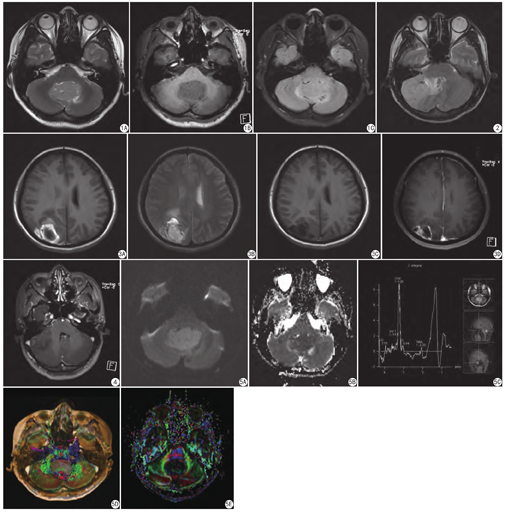

本组病例中,肿瘤实性成分T2WI表现等信号2例,稍高信号12例(图1A);T1WI表现等信号1例,稍低信号13例(图1B);FLAIR序列等信号4例,稍高信号4例(图1C)。8例伴有小血管穿行征(图2)。肿瘤周边或中心均有大小不等囊变区,形态多样;无明显钙化。8例轻度水肿,2例中度水肿,5例无水肿。5例中度强化,4例明显强化,5例斑片状或片絮样轻度强化,1例呈葡萄串样;囊变或坏死区未见强化。位于小脑半球7例与脑膜或小脑幕宽基底相连或贴边走形,未见脑膜尾征。右枕顶叶1例伴出血(图3A、图3B),壁厚、不规则,2个月后复查明显不规则环形强化(图3C、图3D)。CPA区1例伴同侧内耳道扩大,增强后内见多发灶状轻度强化影(图4)。

15例行DWI (b=1000 s/mm2)检查,实性部分均呈高信号(图5A),ADC图呈低信号(图5B),平均ADC值为0.578×10-3 mm2/s ;囊性部分DWI呈低信号。

7例行MRS检查,表现胆碱(Cho)峰明显升高,乙酰天冬氨酸峰(NAA)峰明显降低;5例肌酸(Cr)峰明显降低(图5C),Cho/NAA值(≥4.8)及CHO/Cr值(≥5.1)明显增高。

DTI是一种无创的反映活体脑白质纤维束走形、病理状态及解剖的先进技术,可以判断纤维束被侵润、破坏的程度,对临床诊疗有重要指导意义。各向异性分数(fractional anisotropy,FA)是常用的参数之一。依据脑白质纤维束变化类型及FA彩图相应颜色变化,判断肿瘤的良恶性。肿瘤恶性度越高,纤维束破坏越严重[17,18,19]。该组中3例行DTI检查,可见肿瘤边缘脑白质纤维束移位,部分破坏,FA彩图相应颜色消失。